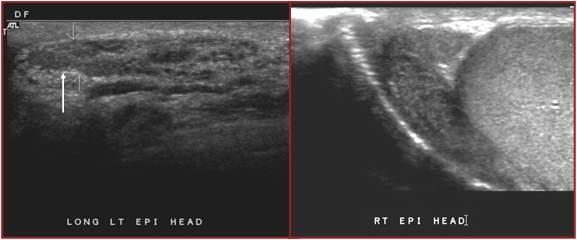

Spermatoceles

AKA Epididymal Cysts

result of dilation of the epididymal tubules

most common condition that causes scrotal pain

possible fever

pyuria

STD

UTI

Epididymitis

inflammation of epididymis usually due to UTI